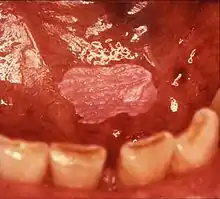

![]() | |

| Leukoplakia on the inside of the cheek | |